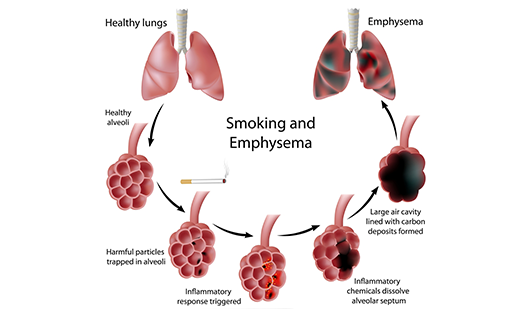

5. Emphysema;

This is the damage of the walls of the air sacs/alveoli resulting in a reduced surface area for gas exchange. Because the surface area fro gas exchange is reduced, the oxygen reaching the brain and heart is also reduced. When this happens, the patient may feel depressed and sluggish.

EVALUATION:

5. Emphysema;

This is the damage of the walls of the air sacs/alveoli resulting in a reduced surface area for gas exchange. Because the surface area fro gas exchange is reduced, the oxygen reaching the brain and heart is also reduced. When this happens, the patient may feel depressed and sluggish.